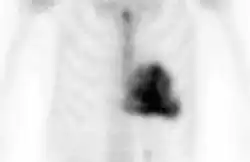

DPD scan

Amyloid deposition in aortic stenosis shown by DPD scan

A DPD scan is a type of nuclear medicine imaging test which uses radioactive technetium-99m (99mTc) and 3,3-diphosphono-1,2-propanodicarboxylic acid (DPD) to diagnose cardiac amyloidosis. The radiopharmaceutical is taken up only in patients with ATTR amyloidosis, making it a useful tool to differentiate from AL amyloidosis.[1]